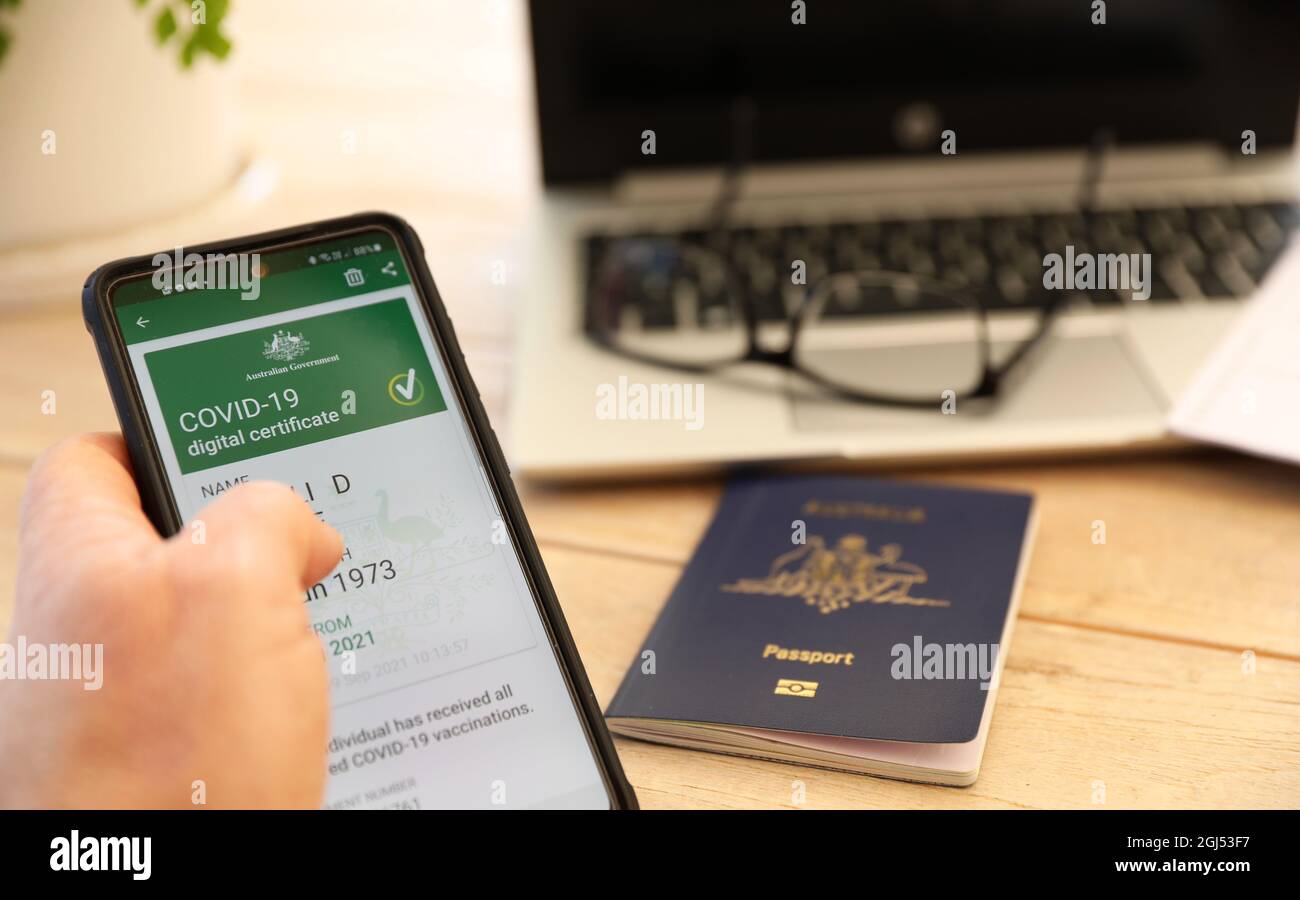

Digital passport vaccination in hi res stock photography and images Alamy

Digital passport vaccination in hi res stock photography and images Alamy